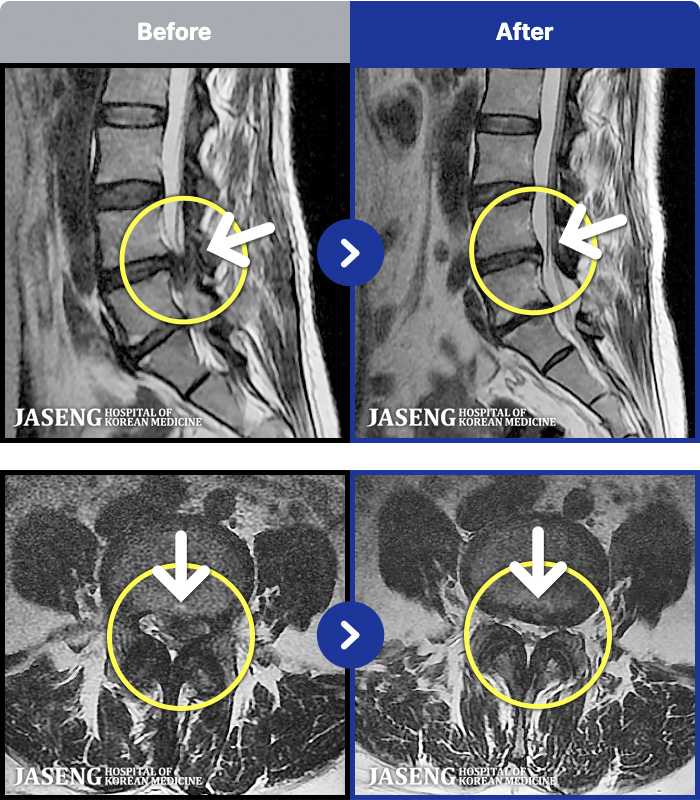

1,237 MRI ũ ʸ Ȯϼ.

1,237